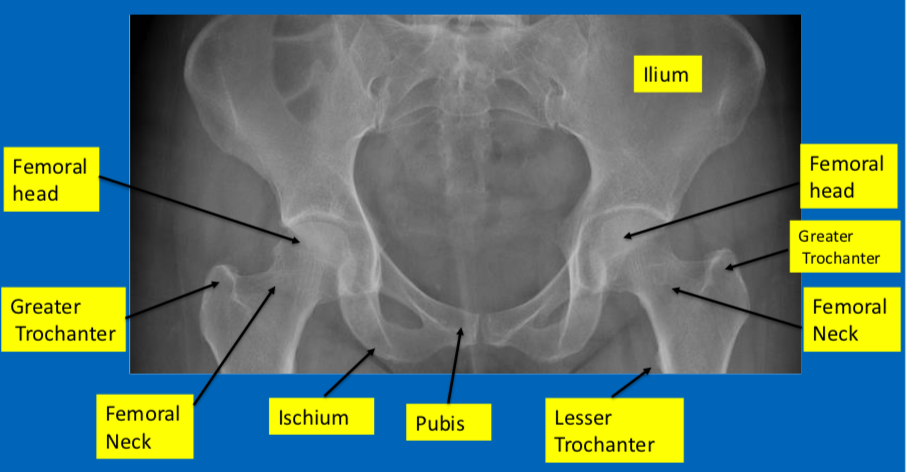

What 3 bones comprise the hip and where are these fused?

Ilium, ischium and pubis → fused at the acetabulum

What classification systems exists for intracapsular NOF#

Explain this classification

Gardens Classification - based on appearance on plain AP x-ray

Identify the blood supply to the femoral head